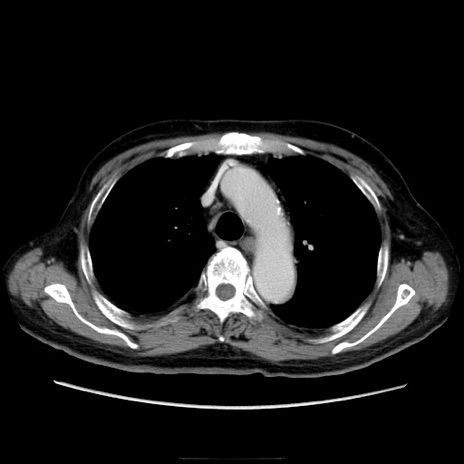

症例21(横断像)

【症例】70歳代男性

【主訴】腹痛

【現病歴】肝硬変・肝細胞癌にてかかりつけの方。約9時間前に食後より腹痛出現。症状が徐々に増悪し、嘔吐出現したため来院。

【既往歴】肝硬変、肝細胞癌(RFA、TACE後)

【身体所見】意識清明、表情苦悶様、BT 36℃、BP 129/78mmHg、P 88bpm、SpO2 97%(RA)、右上腹部から心窩部にかけて圧痛あり、反跳痛なし、筋性防御あり。

【データ】WBC 5800、CRP 0.16